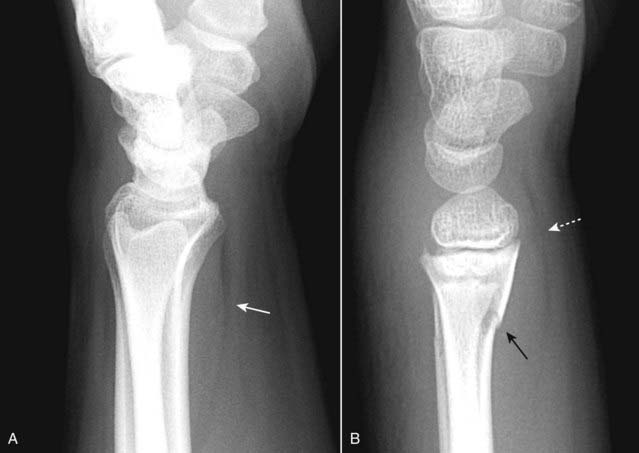

image Colles’ fracture is a fracture of the distal radius with dorsal angulation of the distal radial fracture fragment caused by a fall on the outstretched hand (sometimes abbreviated as FOOSH). There is frequently an associated fracture of the ulnar styloid (Fig. 22-21).

Figure 22-21 Colles’ fracture, frontal (A) and lateral (B) views.

Colles’ fractures are fractures of the distal radius (solid white arrows) with dorsal angulation of the distal radial fracture fragments (solid black arrow) caused by a fall on the outstretched hand (sometimes abbreviated as FOOSH). There is frequently an associated fracture of the ulnar styloid (dotted white arrow).